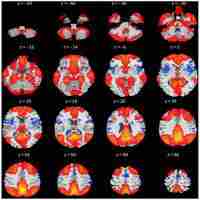

Spatial source phase: A new feature for identifying spatial differences based on complex‐valued resting‐state fMRI data

| Subject Keyword | Journal: Human brain mapping Radiology, Nuclear Medicine and Imaging Complex‐valued Fmri Data Default Mode Network Independent Component Analysis Resting‐state Fmri Data Spatial Source Phase |